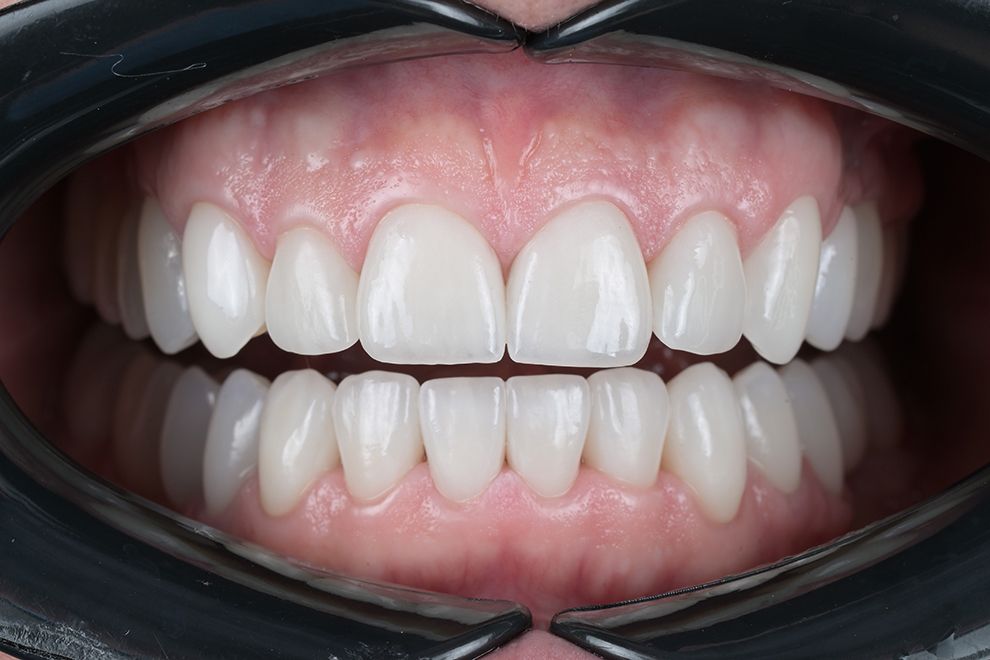

до и после